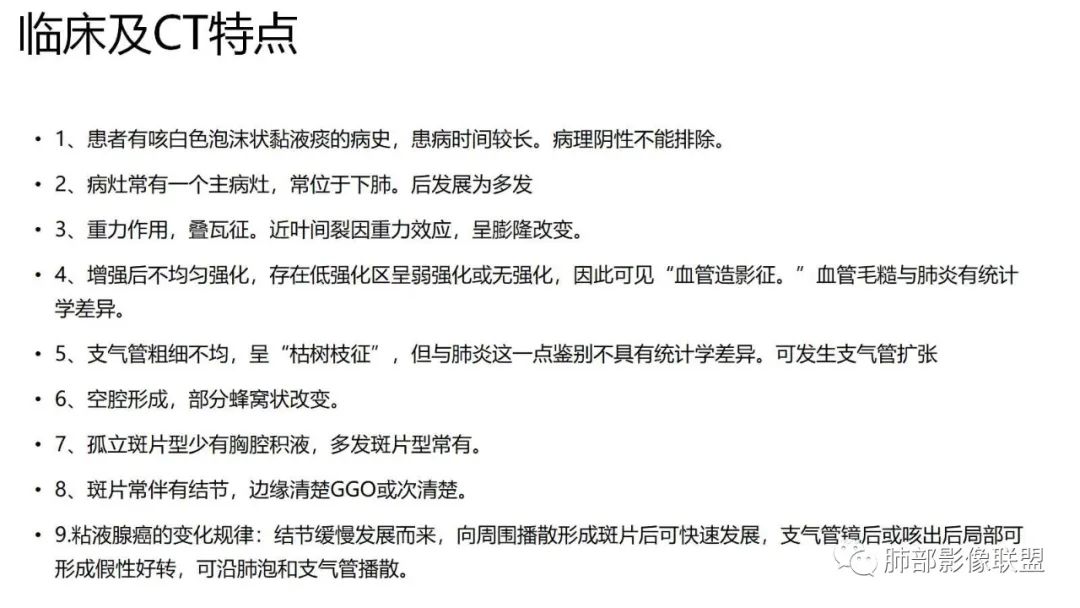

二、肺炎型

1、患者有咳白色泡沫状黏液痰的病史,患病时间较长。病理阴性不能排除。

2、病灶常有一个主病灶,常位于下肺。后沿气道播散为多发病灶。

3、重力作用,叠瓦征。近叶间裂因重力效应,呈膨隆改变。

4、增强后不均匀强化,存在低强化区呈弱强化或无强化,因此可见“血管造影征。”血管毛糙与肺炎有统计学差异。

5、支气管粗细不均,呈“枯树枝征”,但与肺炎这一点鉴别不具有统计学差异。可发生支气管扩张

6、空腔形成,部分蜂窝状改变。

7、孤立斑片型少有胸腔积液,多发斑片型常有。

8、斑片常伴有结节,边缘清楚GGO或欠清楚。

9.粘液腺癌的变化规律:结节缓慢发展而来,向周围播散形成斑片后可快速进展,有时支气管镜后或粘液排出后局部可形成好转的假象。病灶可沿肺泡和支气管播散。